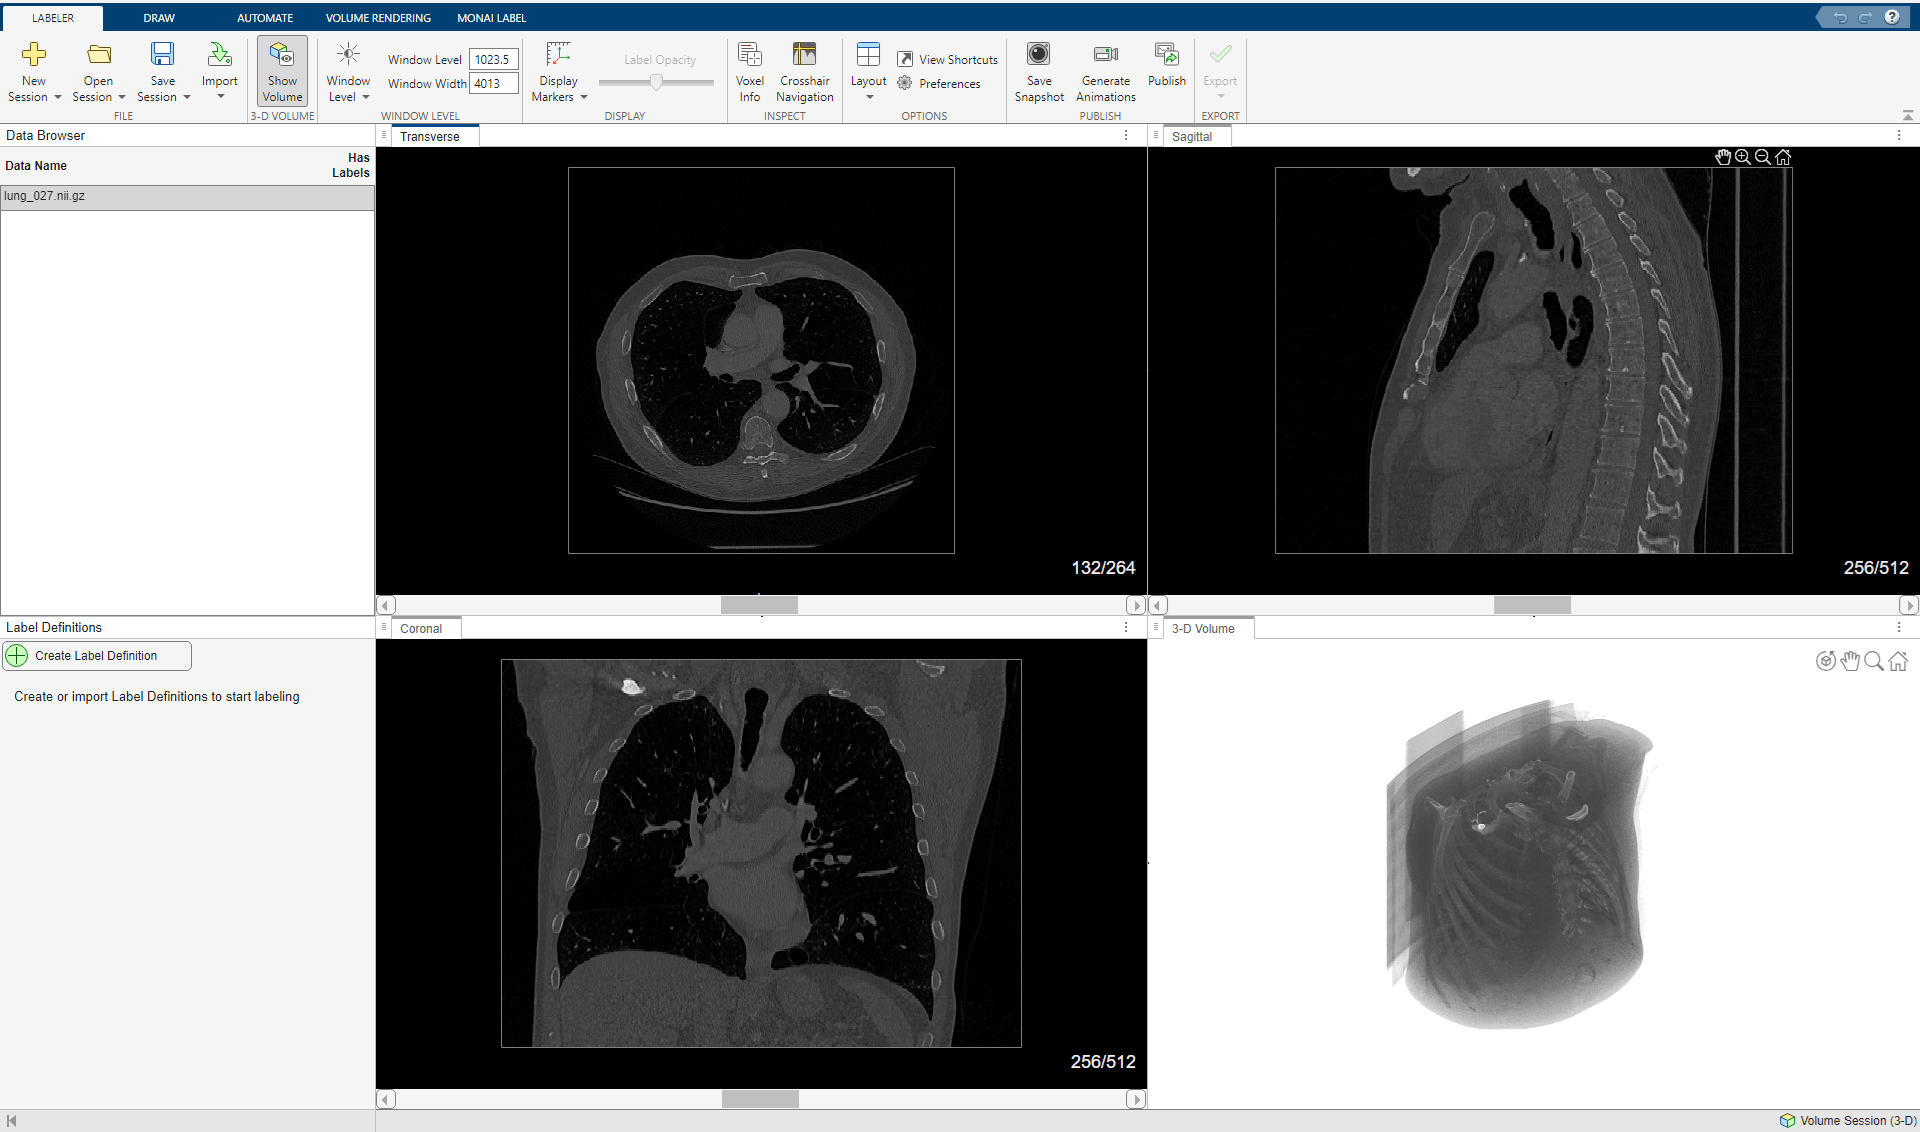

Open Labeling Session and Load Data

Open the Medical Image Labeler app and start a volume labeling session. You can create a new volume session or reopen a previous session. If you create a new session, import the file lung_027.nii.gz from the downloaded data, located in the folder specified by the dataFolder variable. For an example that shows how to create a volume session and import data, see Label 3-D Medical Image Using Medical Image Labeler.